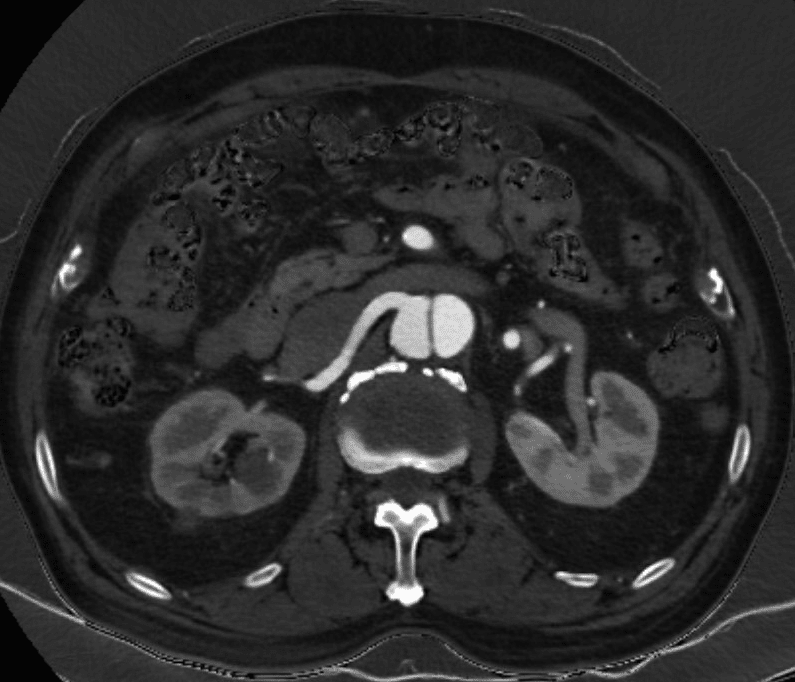

Imaging

Once you suspect a dissection, the next step is to show it. Imaging is done with ultrasound, computed tomography or MRI (and MR Angiography). Of these, the most useful are the CT and MR. But, the ultrasound can examine the flow in the artery. That is often very useful to understand if the function of the artery remained intact or not.